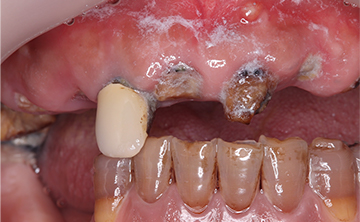

虫歯を放置して10年くらいの症例です。お口の中には、上あごは、一本しか歯が残っておらず、全く噛めないということで来院された患者さんです。痛い時期はどのようにして過ごされたのかと聞くと、とにかく痛み止めとお酒で痛みをごまかして過ごされたそうです。

すごい良く我慢されましたねとお伝えして、今後は、痛い時は安心してご来院くださいと伝えたら、ホッとされていました。小さい頃のトラウマで、とにかく歯科医院に行くことが怖かったそうです。

10年間虫歯を放置すると虫歯というより、歯が無くて噛めないので、咀嚼という問題が発生します。食べ物をお口の中へ入れても噛めないので、そのまま丸のみという食事になってしまうと胃や腸への負担は必須となり、癌や他の疾患へかかりやすますね。